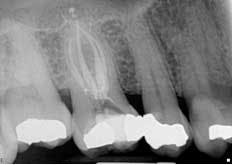

Second visit The patient returned to City Endodontics for treatment asymptomatic two weeks later. Rubber dam isolation and access were modified with the DOM; exploration of the distal anatomy was revisited. The distal canal was troughed with a fine diamond tip from an ultrasonic machine (Coltene), and a disto-buccal (DB2) canal located with the aid of the NaOCl 6% bubble test and anatomical landmarks. The DB2 canal was cleaned and shaped to length using same technique used for the other canals at the initial visit. The apex locator Root ZX II was used to confirm presence of an additional canal and reconfirm length for other canals. A check film was taken with files in all five canals to verify presence of five separate orifices and apices. A master cone for all five canals with gutta percha fit to working length was exposed. (Fig. 3)Fig. 3: Master cone fit radiograph of tooth No. 3 highlighting five canals

Figs. 4 and 5: Radiographs of tooth No. 3: Five-canal molar with two mesial and two distal canals present

The obturation technique included warm vertical condensation with continuous wave and AH-plus sealer and backfilled all the canals to their respective orifice. Cotton and cavit g temporary restoration were again placed more than 3 mm from the occlusal surface to prevent coronal micro-leakage in the access cavity. The occlusion checked, postoperative instructions were written and verbally given. Two periapical radiographs were exposed to illustrate the unique anatomy. (Figs. 4 and 5)